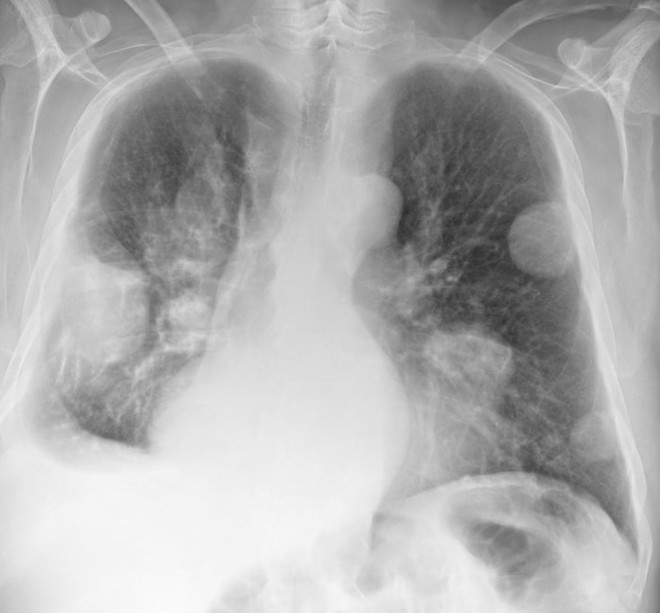

MRI

Pleomorphic rhabdomyosarcoma adult